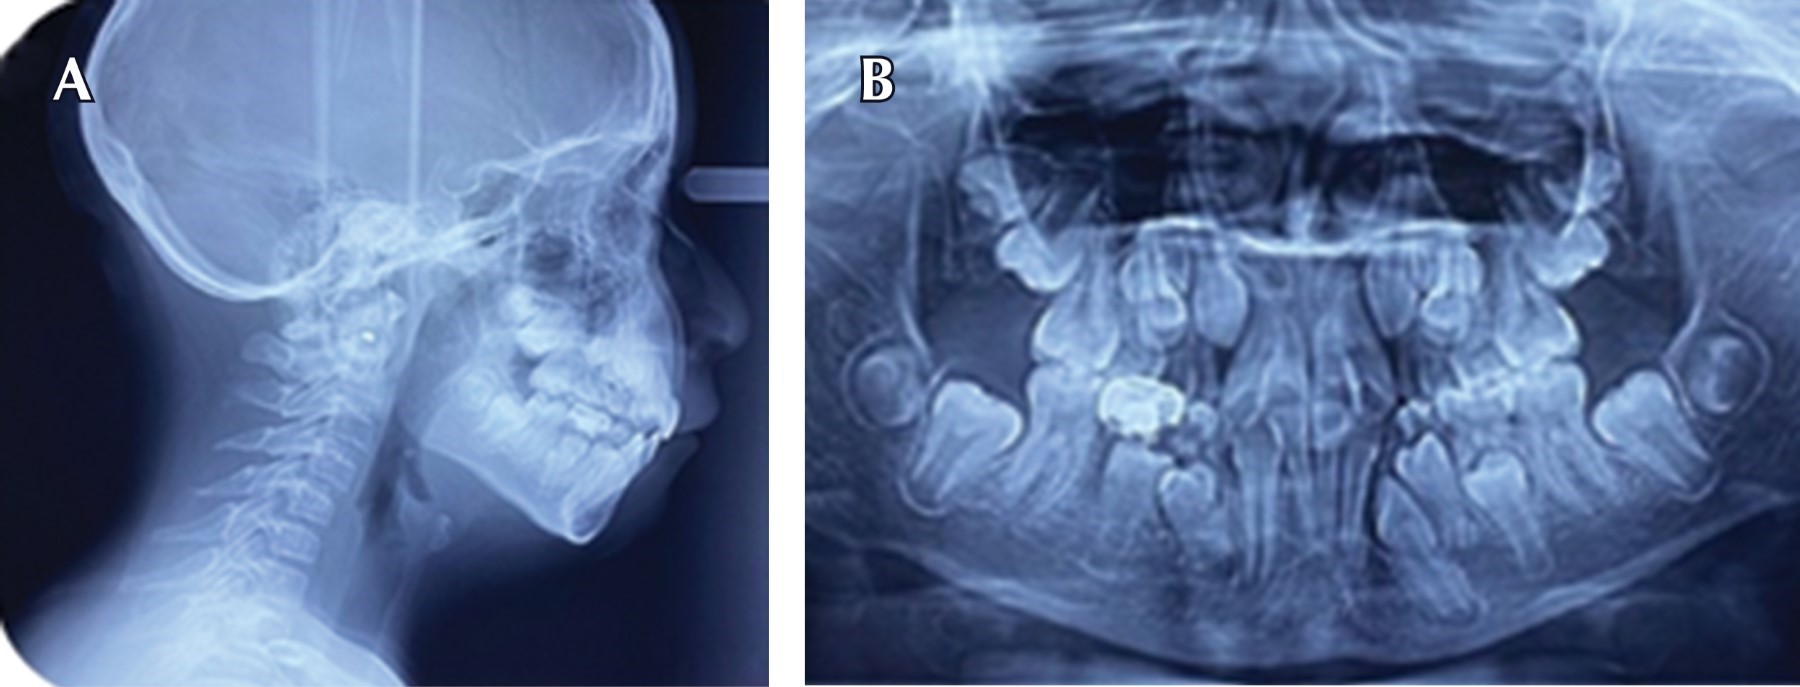

El estado actual del paciente es estable, anteriormente ya había sido atendida odontológicamente y su experiencia fue negativa. De acuerdo con la Academia Americana de Anestesiología13 se clasificó como ASA II (paciente con enfermedad sistémica leve o compensada). En la exploración clínica extraoral se observó cara redonda, tercio medio aumentado, ligera asimetría facial, perfil convexo y retrognatismo mandibular (Figura 2). La paciente tiene una conducta no cooperadora y se clasifica en una escala de Frankl 2,14 por lo que la exploración oral inicial se realizó fuera del sillón dental. Las características clínicas intraorales observadas fueron: boca simétrica con mal posición dentaria por falta de espacio, retraso en la erupción dentaria, microdoncia, micrognatia, línea media desviada, presencia de dentición mixta, arcadas de forma cuadrada, mucosas hidratadas, clase I molar derecha e izquierda y apiñamiento dental (Figura 3). Se solicitó radiografía lateral de cráneo y el análisis vertebral indicó un estadio CS3, los bordes inferiores de C2 y C3 mostraron concavidades y C4 superficies planas (Figura 4A). En la radiografía panorámica se observó agenesia de órgano dentario 42 (Figura 4B).

Figura 4